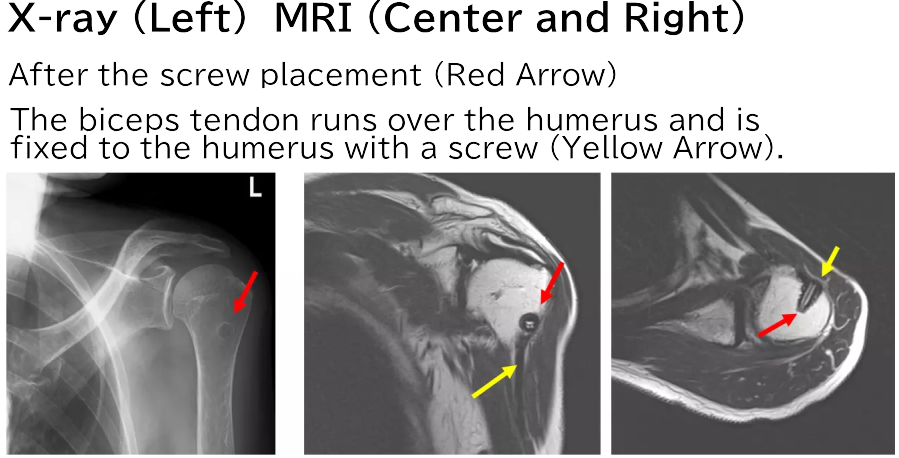

X-rays and MRI scans were taken, confirming that the biceps tendon had been securely attached to the humerus as a result of the surgery.

On the MRI, fluid accumulation in the intertubercular groove of the long head of the biceps tendon is observed, along with injuries to the subscapularis tendon and supraspinatus tendon. Below, the actual MRI image is presented.